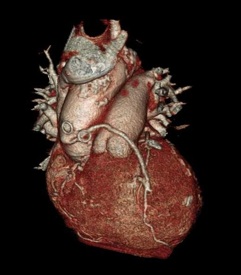

Durch die hochauflösende Aufnahmetechnik gelingt es die

Koronargefäße, Verkalkungen im Bereich der Koronargefäße  sowie

Bypassgefäße und weitere wichtige Herzstrukturen darzustellen.

*  Darstellung der Koronararterien

*  Darstellung aortokoronarer Bypässe